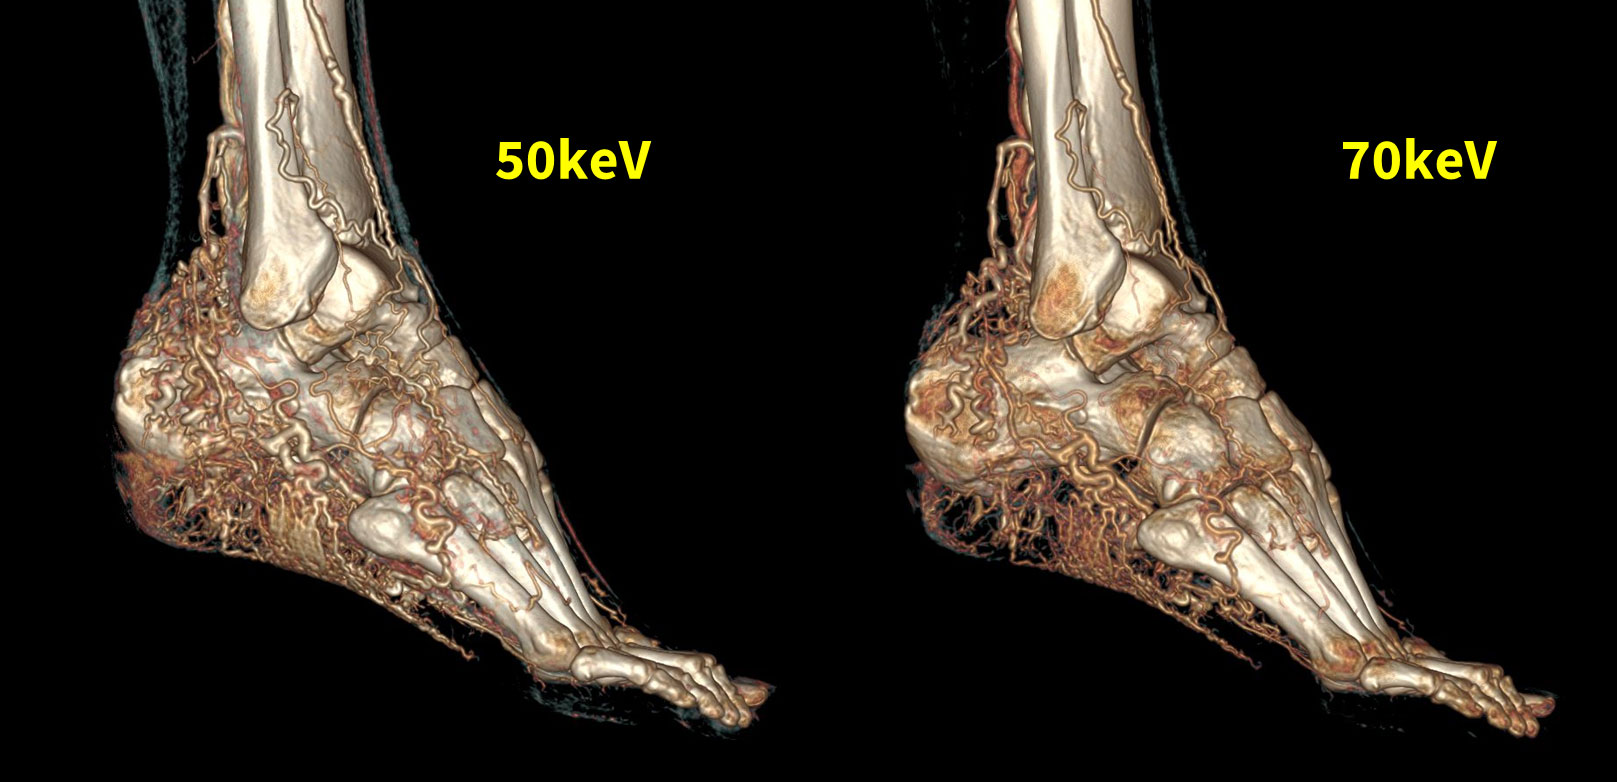

動静脈奇形や動静脈瘻の撮影では、ナイダスと呼ばれる異常血管網や動静脈シャントが原因で通常のCT-Angioの撮影では十分に撮影タイミングが得られないことがある。特に、四肢末梢血管に存在する血管は栄養血管が細く、側副血行路までの描出は困難な場合がある。Fig7は下肢AVMをDECTで撮影した症例である。50keVの仮想単色X線画像で再構成した場合、70keVと比較して末梢血管の描出を向上させることができた。

RevolutionCT_Minamitohoku08.jpg

Fig7, 低keVを用いてタイミングが難しいAVMの描出